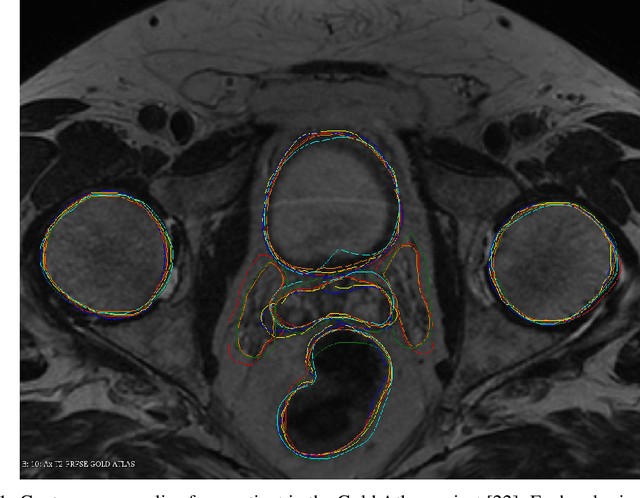

Abstract:This work presents a study on label noise in medical image segmentation by considering a noise model based on Gaussian field deformations. Such noise is of interest because it yields realistic looking segmentations and because it is unbiased in the sense that the expected deformation is the identity mapping. Efficient methods for sampling and closed form solutions for the marginal probabilities are provided. Moreover, theoretically optimal solutions to the loss functions cross-entropy and soft-Dice are studied and it is shown how they diverge as the level of noise increases. Based on recent work on loss function characterization, it is shown that optimal solutions to soft-Dice can be recovered by thresholding solutions to cross-entropy with a particular a priori unknown threshold that efficiently can be computed. This raises the question whether the decrease in performance seen when using cross-entropy as compared to soft-Dice is caused by using the wrong threshold. The hypothesis is validated in 5-fold studies on three organ segmentation problems from the TotalSegmentor data set, using 4 different strengths of noise. The results show that changing the threshold leads the performance of cross-entropy to go from systematically worse than soft-Dice to similar or better results than soft-Dice.

Abstract:This paper presents a study on the soft-Dice loss, one of the most popular loss functions in medical image segmentation, for situations where noise is present in target labels. In particular, the set of optimal solutions are characterized and sharp bounds on the volume bias of these solutions are provided. It is further shown that a sequence of soft segmentations converging to optimal soft-Dice also converges to optimal Dice when converted to hard segmentations using thresholding. This is an important result because soft-Dice is often used as a proxy for maximizing the Dice metric. Finally, experiments confirming the theoretical results are provided.

Abstract:We study two of the most popular performance metrics in medical image segmentation, Accuracy and Dice, when the target labels are noisy. For both metrics, several statements related to characterization and volume properties of the set of optimal segmentations are proved, and associated experiments are provided. Our main insights are: (i) the volume of the solutions to both metrics may deviate significantly from the expected volume of the target, (ii) the volume of a solution to Accuracy is always less than or equal to the volume of a solution to Dice and (iii) the optimal solutions to both of these metrics coincide when the set of feasible segmentations is constrained to the set of segmentations with the volume equal to the expected volume of the target.